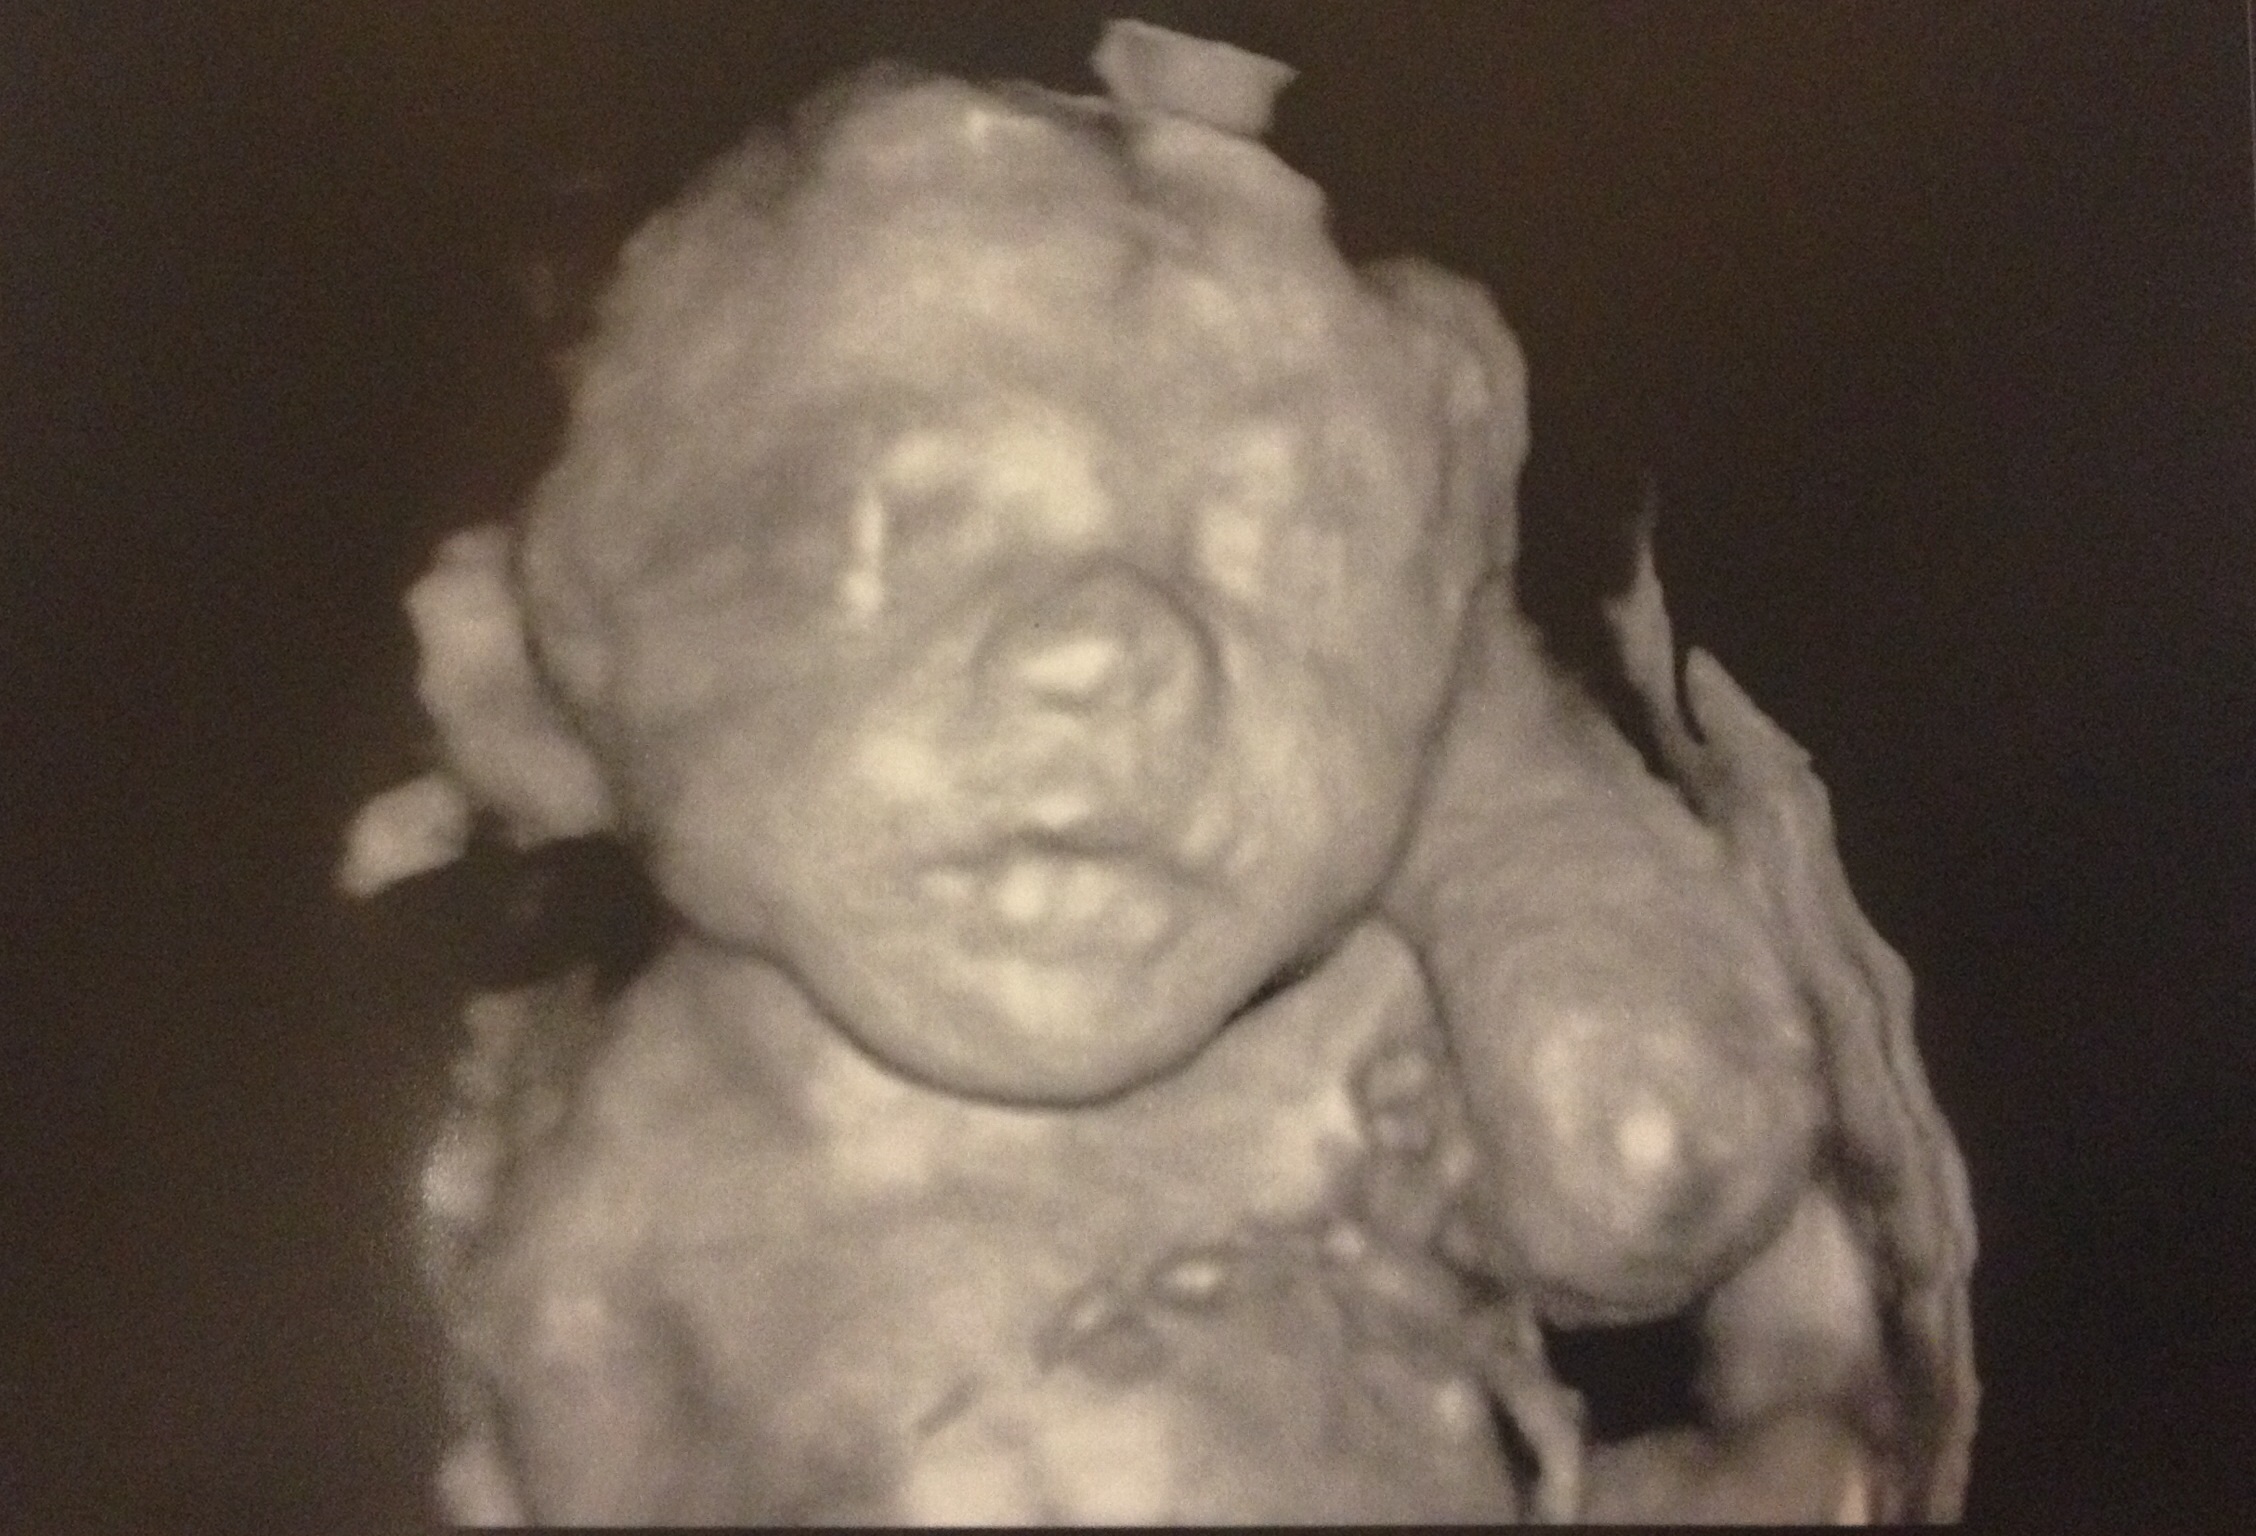

25w4d.... measuring EXACTLY on pace at 25w4d! My husband and I can absolutely start seeing a resemblance to my side of the family (versus my husband's) in her face...while my family sadly thinks I'm out of my mind and that these photos are super creepy lol. They say of course they will love her more than anything when she arrives but for now she looks only like a little alien still. I refuse to let them ruin my fun! Next sonogram in 3 weeks Not high risk pregnancy but my docs like to be "proactive" and do sonograms at each monthly visit... for a peek at my LO each month, I'll gladly pay a copay!

Oh, and the u/s pic is 3d, the MFM center did it and turned it on